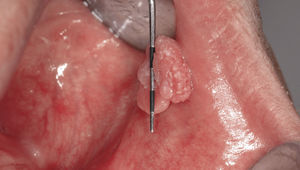

Papiloma de células escamosasSi bien en la bibliografía más reciente se insiste reitera-damente en que el papiloma de células escamosas y la verruga vulgar son clínicamente indistintos se ha optado por exponerlos de forma separada en el presente trabajo de revisión. El papiloma de células escamosas muestra un pico de incidencia entre la tercera y la quinta década de la vida. Suele tratarse de una lesión solitaria de crecimiento relativamente rápido hasta alcanzar un diámetro de 1–5 mm7. Los papilomas de células escamosas orales suelen tener una consistencia blanda y a menudo son pediculados. Son exofíticos en forma de coliflor con pro-longaciones blanquecinas y una superficie papilar a ve-rrugosa. Se localizan sobre todo en el paladar blando, la lengua, el frenillo lingual y el labio inferior7 (figs. 1–3, fig. 4a, fig. 4b, fig. 4c, fig. 4d, fig. 4e). Los VPH tipo 6 y 11 desempeñan un papel importante en estos tumores desde el punto de vista etiopatogénico7,18.

Condiloma acuminadoEsta variante de las verrugas (sinónimos: verrugas geni-tales, verrugas venéreas) se transmite sobre todo a través de relaciones sexuales orogenitales (anales), por autoinoculación o por transmisión materno-filial durante el parto7. Los condilomas son más frecuentes en pacientes infectados por el VIH8. En la cavidad oral se localizan principalmente en la zona de la mucosa labial, en el paladar blando, el suelo de la boca y el frenillo lingual7,8. Los condilomas suelen aparecer a menudo agrupados. El tamaño de algunas alteraciones aisladas puede ser mayor que el de los papilomas o de las verrugas. Los VPH implicados más frecuentemente en esta variante de neoplasias son los tipos 6 y 117,18.